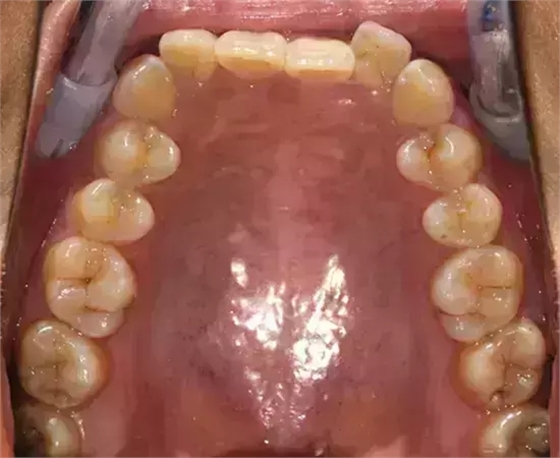

上下牙列擁擠,磨牙尖牙Ⅱ 類關(guān)系,3 度的深覆牙合,上頜中切牙伸長內(nèi)傾拔除上頜雙側(cè)的第一前磨牙,先粘上頜高轉(zhuǎn)矩的自鎖托槽排齊牙列,唇向開展上頜切牙,有一定的覆蓋,粘下頜標準轉(zhuǎn)矩托槽,上頜 1, 2 之間植入種植支抗壓入,同時后牙 5, 6 之間植入種植支抗內(nèi)收前牙,打開咬合關(guān)閉間隙。治療關(guān)鍵:前牙轉(zhuǎn)矩的控制第 1 個月 上頜粘上 Damon Q 高轉(zhuǎn)矩托槽,上 .014 熱激活 NiTi 絲。第 3 個月 上換 .014 x .025 熱激活 NiTi 絲。第 5 個月 上頜基本排齊,覆蓋增大,上換 .017 x .025 NiTi絲,下頜粘托槽,下 .014 熱激活 NiTi 絲。第 7 個月 上 .017 x .025 NiTi 絲加搖椅,下?lián)Q .014 x .025 熱激活 NiTi 絲第 9 個月 上頜換 .019 x .025 NiTi 絲加搖椅,下頜換 .017 x .025 NiTi 絲第 11 個月 下頜換 .019 x .025 加搖椅,上頜 1, 2 之間, 5, 6 之間植入種植釘,下頜出現(xiàn)散隙。第 13 個月 上頜換 .019 x .025ss 加搖椅,前牙種植釘用 Power Chain 壓低前牙(每側(cè) 100g),后牙種植釘關(guān)閉間隙(每側(cè) 150g),下?lián)Q .019 x .025ss,Power Chain 關(guān)閉間隙。第 19 個月 上頜前牙基本壓低到位去除前牙種植釘,繼續(xù)用關(guān)閉間隙,下頜散隙關(guān)閉。